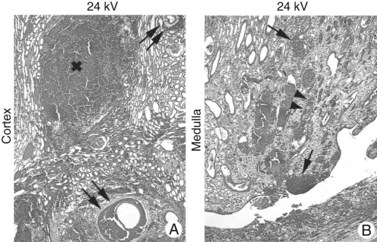

Figure 48–27 This series of light microscope panels depicts the injury seen in the cortex and medulla from an animal treated with 2000 shockwaves at 24 kV by an unmodified Dornier HM3 lithotripter. A and B illustrate extensive injury in both cortex and medulla. Within the cortex, disruption of arterial walls with hemorrhage (double arrows) is noted near sites of intraparenchymal bleeding (x). The first site of injury appears to occur in the renal medulla, where damage is noted to small vessels, which causes intraparenchymal hemorrhage (arrows) adjacent to damaged collecting ducts (arrowheads).

Figure 48–25 Light micrographs of an acute shockwave lithotripsy (SWL)-induced lesion at F2 (A) and subsequent chronic changes at a similar site 3 months after SWL treatment (B). Each pig kidney was treated with 2000 shockwaves at 24 kV by an unmodified Dornier HM3 lithotripter. The acute lesion is characterized by numerous sites of hemorrhage (arrows) that extend from an individual renal papilla (asterisk) to the outer cortex of the kidney. Note a subcapsular hematoma (double arrows, A). The tissue section in B is similar in location to that seen in A but is shown at 3 months after SWL. A rectangle outlines the site of F2. Within that region there is complete loss of the renal papilla (the asterisk indicates where it should be), and only scar tissue is found in the adjacent cortical tissue (arrow).